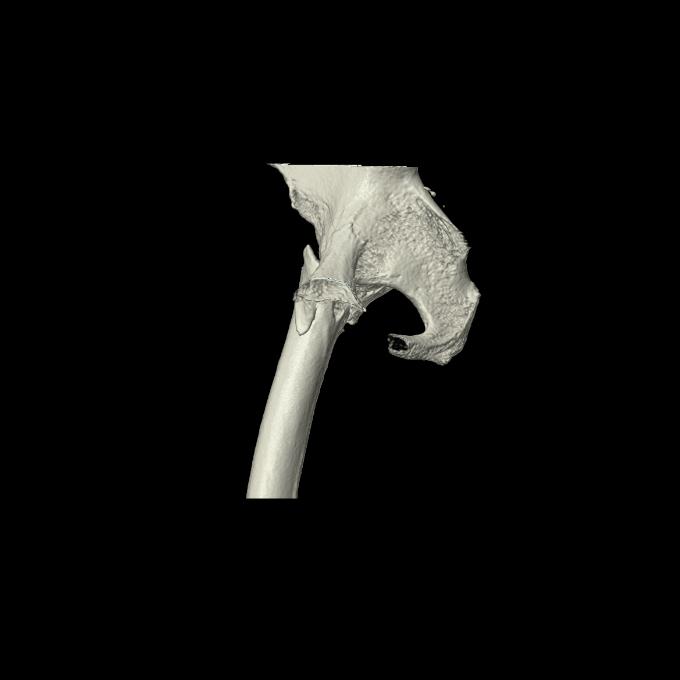

110286 2/17 股関節 2R 74歳女性 右人工骨頭

102903 股関節 2R 1/28 +股関節 2R 1/29 78歳女性 左人工骨頭

100703 1/27 両股正面+軸 1/29 両股正面+軸 94歳女性 パンソンロン

46666 1/28 両股正面+軸と 1/26 右手関節 2R 76歳女性 右転子部骨折

37 1/18 両股正面+軸 1/22 2R 86歳女性 右転子下

82084 1/14 1/20 股関節 2R 78歳男性 右人工骨頭

102811 1/13 股関節 2R 1/19 2R 80歳女性 右DHS

91569 3/25 両股正面とラウエン 70歳女性 人工骨頭+バンクーバー